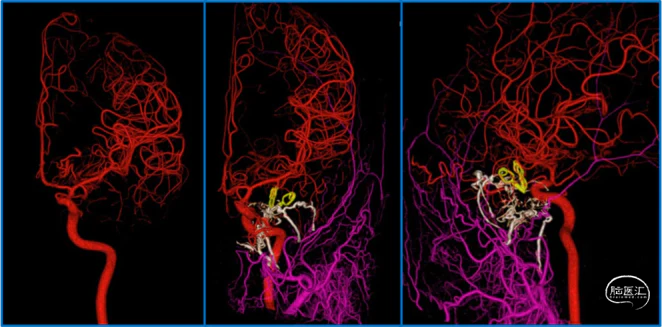

典型病例

![]()

蝶顶窦旁DAVF属于Borden III型,需要积极外科治疗。

蝶顶窦旁DAVF,可吸引前和中颅窝硬膜的所有动脉参与供血。其中颈内动脉及其分支的供血可以使用显微外科技术阻断;颈外动脉的供血动脉可以使用介入栓塞技术阻断。

介入栓塞眼动脉供血的要点:超选左侧眼动脉,跃过视网膜中央动脉,栓塞脑膜回返动脉对DAVF的供血。目的:保护眼动脉视网膜中央动脉分支,避免后期栓塞颈外动脉的供血动脉时损伤眼动脉。

引流静脉是否引流进入海绵窦,决定DAVF诊断为“颈动脉-海绵窦动静脉瘘”还是“蝶顶窦旁DAVF”。

静脉的引流路径决定患者静脉高压的临床表现,预后风险,治疗方案。

稳妥的外科治疗方案:先介入栓塞颈外动脉的供血动脉,然后显微手术切断颈内动脉的供血动脉,阻断引流静脉,电凝封闭硬膜瘘口。

神经内镜可以辅助确认颞极深部的引流静脉,避免残留引流静脉。